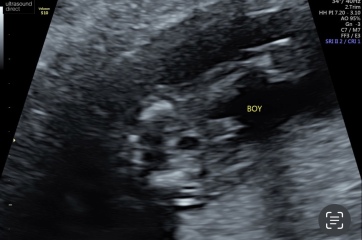

Had our gender scan today….another wee boy to add to our gang

Forgot to attach the pictures

I’ll add my potty shots below aswell 👶🏼💙

I'll add my potty shot for comparison purposes and so we're all reassured we're looking at the right thing 😋